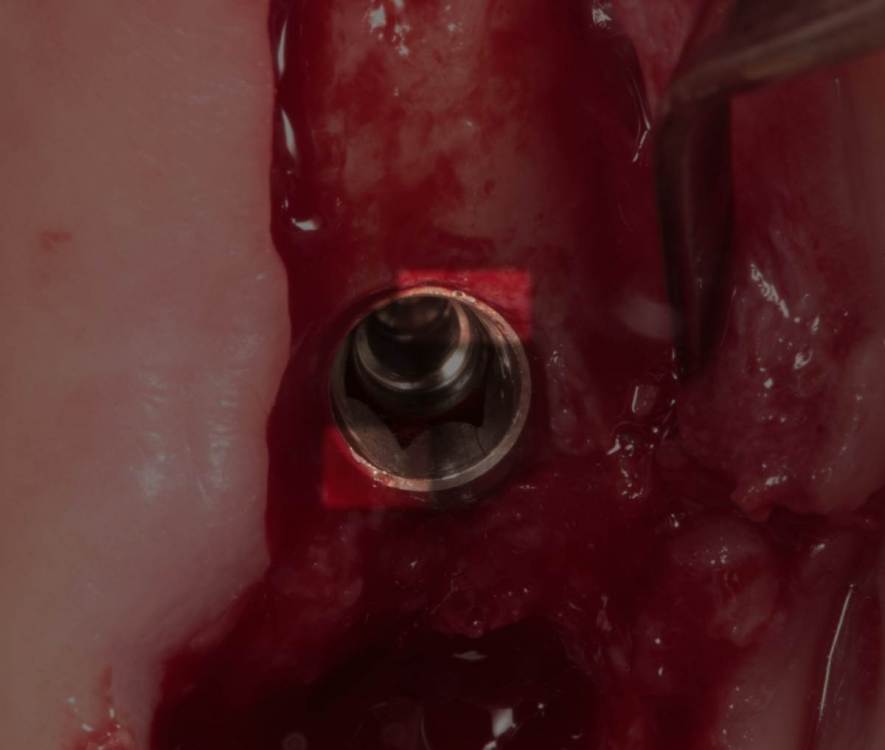

Женька Опубликовано 24 июля, 2023 Поделиться Опубликовано 24 июля, 2023 Тема ради одной фотки конечно, но всё-таки вопрос есть. Говорят МСТ профайлер не задевает стенки имплантата. Кмк, всё-таки задевает. Или всё-таки кажется? По кейсу: 2 имплантата, оба по шаблону. Черт дёрнул пройти глубже чем планировал в 1.6, фрезой перфо не создал, но кортикалку в ноль убрал. И при отслойке всё-таки порвал немного. Тампонировал губками, пробы отрицательные. Вроде нигде не перемудрил в этот раз, @АнтонТЛТ ? 3 Ссылка на комментарий

Raystom Опубликовано 24 июля, 2023 Поделиться Опубликовано 24 июля, 2023 @Женькакажется. Там юбка направляющего пина не даёт портить стенки. Ссылка на комментарий

Женька Опубликовано 24 июля, 2023 Автор Поделиться Опубликовано 24 июля, 2023 @Raystom я про эти участки Ссылка на комментарий

Raystom Опубликовано 24 июля, 2023 Поделиться Опубликовано 24 июля, 2023 @Женька хотя да, если присмотреться, то есть небольшое снятие фаски шейки по внутреннему контуру. Ссылка на комментарий